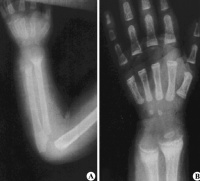

③四肢:“手镯”及“脚镯”;开始行走后,(“O”型)或(“X”型)腿,长骨可发生青枝骨折。

①X线:钙化带模糊,干骺端增宽,边缘呈毛刷状或杯口状改变。

本病主要是引起婴儿抬头、坐、站、行走都较晚。关节松弛而有过伸现象,大脑皮层功能异常条件反射形成缓慢,语言发育落后,贫血等症状。 在一些比较严重的佝偻病的患儿中,还会出现其他的骨骼变形,如鸡胸、漏斗胸、X型腿、O型腿、肋串珠、手镯和脚镯等。

2、中度:可见典型的串珠、手镯、肋软骨沟、轻度或中度的鸡胸、漏斗胸、O或X型腿,也可有囱门晚闭、出牙迟缓等明显的改变。

2、激期:常见于3个月至2岁的小儿。有明显的夜惊、多汗、烦躁不安等症状。同时可有中度的骨骺改变体征。X线片可见临时钙化带模糊消失,干骺端增宽,边缘不整呈云絮状,毛刷状或杯口状,骨骺软骨加宽。血钙、血磷均降低,硷性磷酸酶增高。